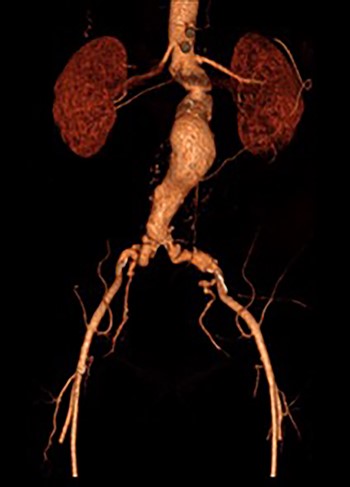

A 65-year-old man was admitted electively with a 55-mm infrarenal abdominal aortic aneurysm (AAA). Computed tomography (CT) angiography had demonstrated aneurysm morphology that was suitable for EVAR, although there were some adverse features with the neck (16 mm length, but conical and angulated) (Fig. 1). His past medical history was significant and included type 2 diabetes mellitus, obesity (body mass index of 32.2 kg/m2), hypercholesterolaemia, ischaemic heart disease (with coronary artery bypass graft) and associated moderate left ventricular systolic dysfunction, chronic obstructive pulmonary disease, arthritis and poor mobility requiring a wheelchair. Following discussion in the local multidisciplinary team meeting a decision was made to offer percutaneous EVAR under local anaesthesia.

3D reconstruction CT scan, at 6-week interval from index procedure.

The patient was transferred to the high-dependency unit for observation during the thrombolysis. After 4-h, the patient was taken back to Interventional Radiology department for a check angiogram (Fig. 3). This demonstrated a fully re-canalized aorto-iliac system with no distal thrombotic or embolic complications. The thrombolysis infusion was stopped at this stage. In the post-operative period, anticoagulation has been continued with Apixaban. A CT scan 6 weeks post-procedure has confirmed ongoing patency of the endograft with no visible thrombus (Fig. 4).